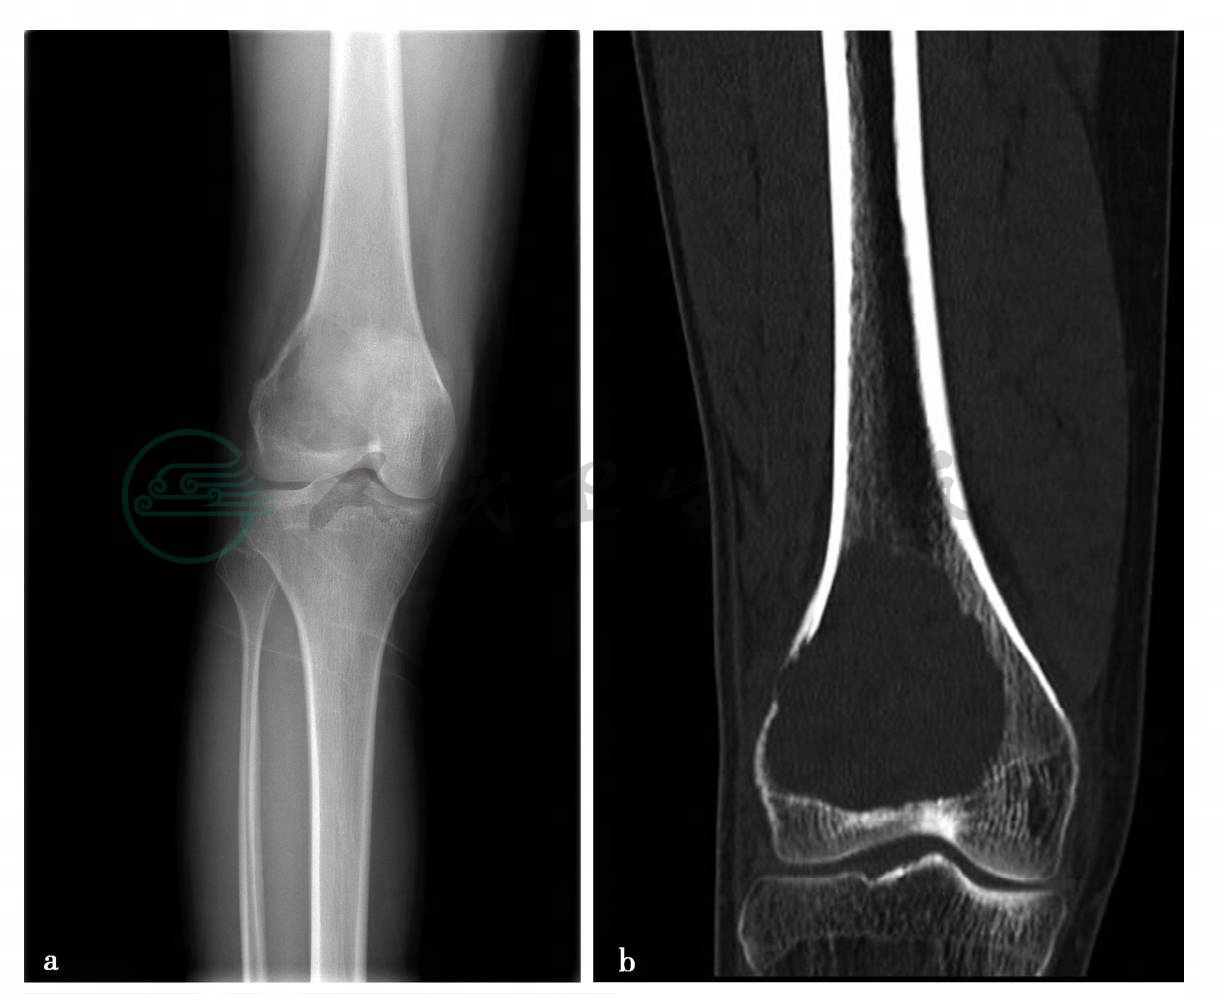

(3)病例2:

MRI平扫。

图3 图3d~f,MRI示右股骨远端膨胀性骨质破坏,边界较清楚,病灶组织向后侧略突出皮质外。图3d,病灶内容物在T1WI上呈低信号。图3e、f,在T2WI脂肪抑制像上呈略高信号,在远侧病灶内有多个圆形的更高小囊状信号影,无液-液平面。无明确骨膜反应